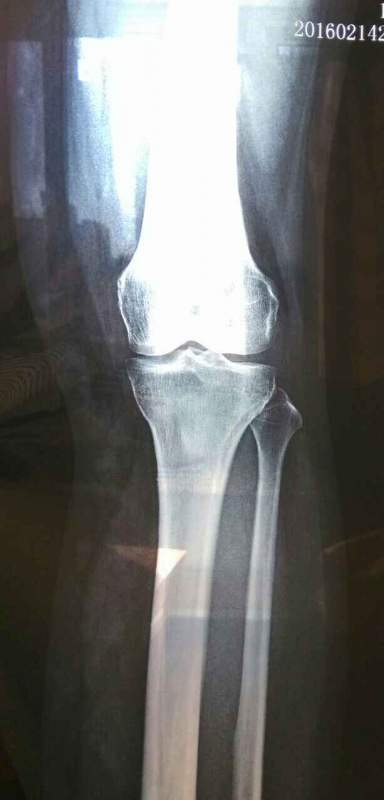

55岁女性,膝盖不舒服,尤其上下楼梯,休息不动又没感觉。请教各位,影像来看问题严重么 发自小木虫Android客户端 |